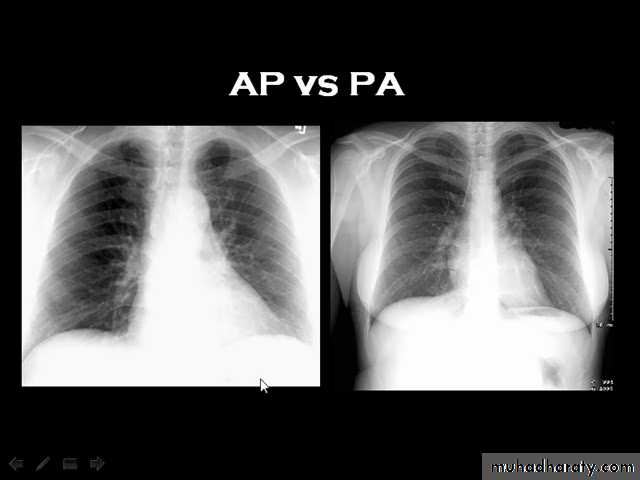

Techniques - Projection

P-A (relation of x-ray beam to patient)

Supine view (AP)

Lateral view .

lateral decubitus .

(in which the pt put on the suspected side & X-ray is taken (such as in pleural effusion).

Routine Examination includes

P-A view , Other supplementary views are done according to the case. So all Patients admitted to hospital should have P-A X-ray In standing erect view in complete inspiration